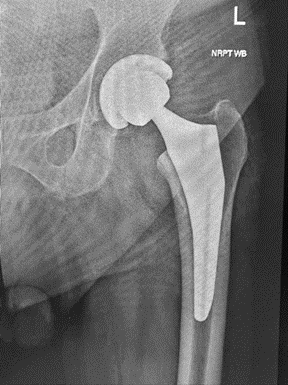

R: Si effettua una sostituzione totale dell'anca (chiamata anche artroplastica totale dell'anca), l'osso e la cartilagine danneggiati vengono rimossi e sostituiti con componenti protesici.

• La testa del femore danneggiata viene rimossa e sostituita con uno stelo di metallo che viene inserito nel centro cavo del femore. Lo stelo femorale può essere cementato o "inserito a pressione" nell'osso.

• Una sfera di metallo o ceramica è posta sulla parte superiore dello stelo. Questa sfera sostituisce la testa del femore danneggiata che è stata rimossa.

• La superficie cartilaginea danneggiata dell'alveolo (acetabolo) viene rimossa e sostituita con un alveolo metallico. A volte vengono utilizzate viti o cemento per tenere in posizione le varie componenti della protesi. Tra l’alveolo e la testa femorale in cromo o titanio, viene sempre utilizzato uno strato di polietilene preventivamente trattato con radiazioni per reticolare i radicali liberi nella plastica e così diminuire l'incidenza dell'usura dovuta a fenomeni di ossidazione. In altre parole, il trattamento con radiazioni, limita o rallenta il processo di usura e deterioramento del polietilene. In caso di deterioramento, grazie alla natura modulare di ogni componente, potrà essere necessario, col tempo, sostituire solo questa parte.

D: Come vengono fissate le protesi?

R: Vi sono due tecniche distinte. La prima prevede una fissione a pressione, con la seconda si fa uso di cementi.

L'uso della tecnica a pressione, è legata alla qualità e consistenza delle ossa esistenti. Col tempo, nuovo osso crescerà intorno alla protesi e tenderà a renderla più duratura. Le protesi non cementate comportano una maggiore incidenza di fratture femorali al momento dell'inserimento, ecco perché parlavo dell’importanza dell’integrità dell’osso. Contrariamente nelle persone anziane, con ossa fragili, si tende a usare il cemento. In questo caso vengono spesso utilizzate protesi in titanio.